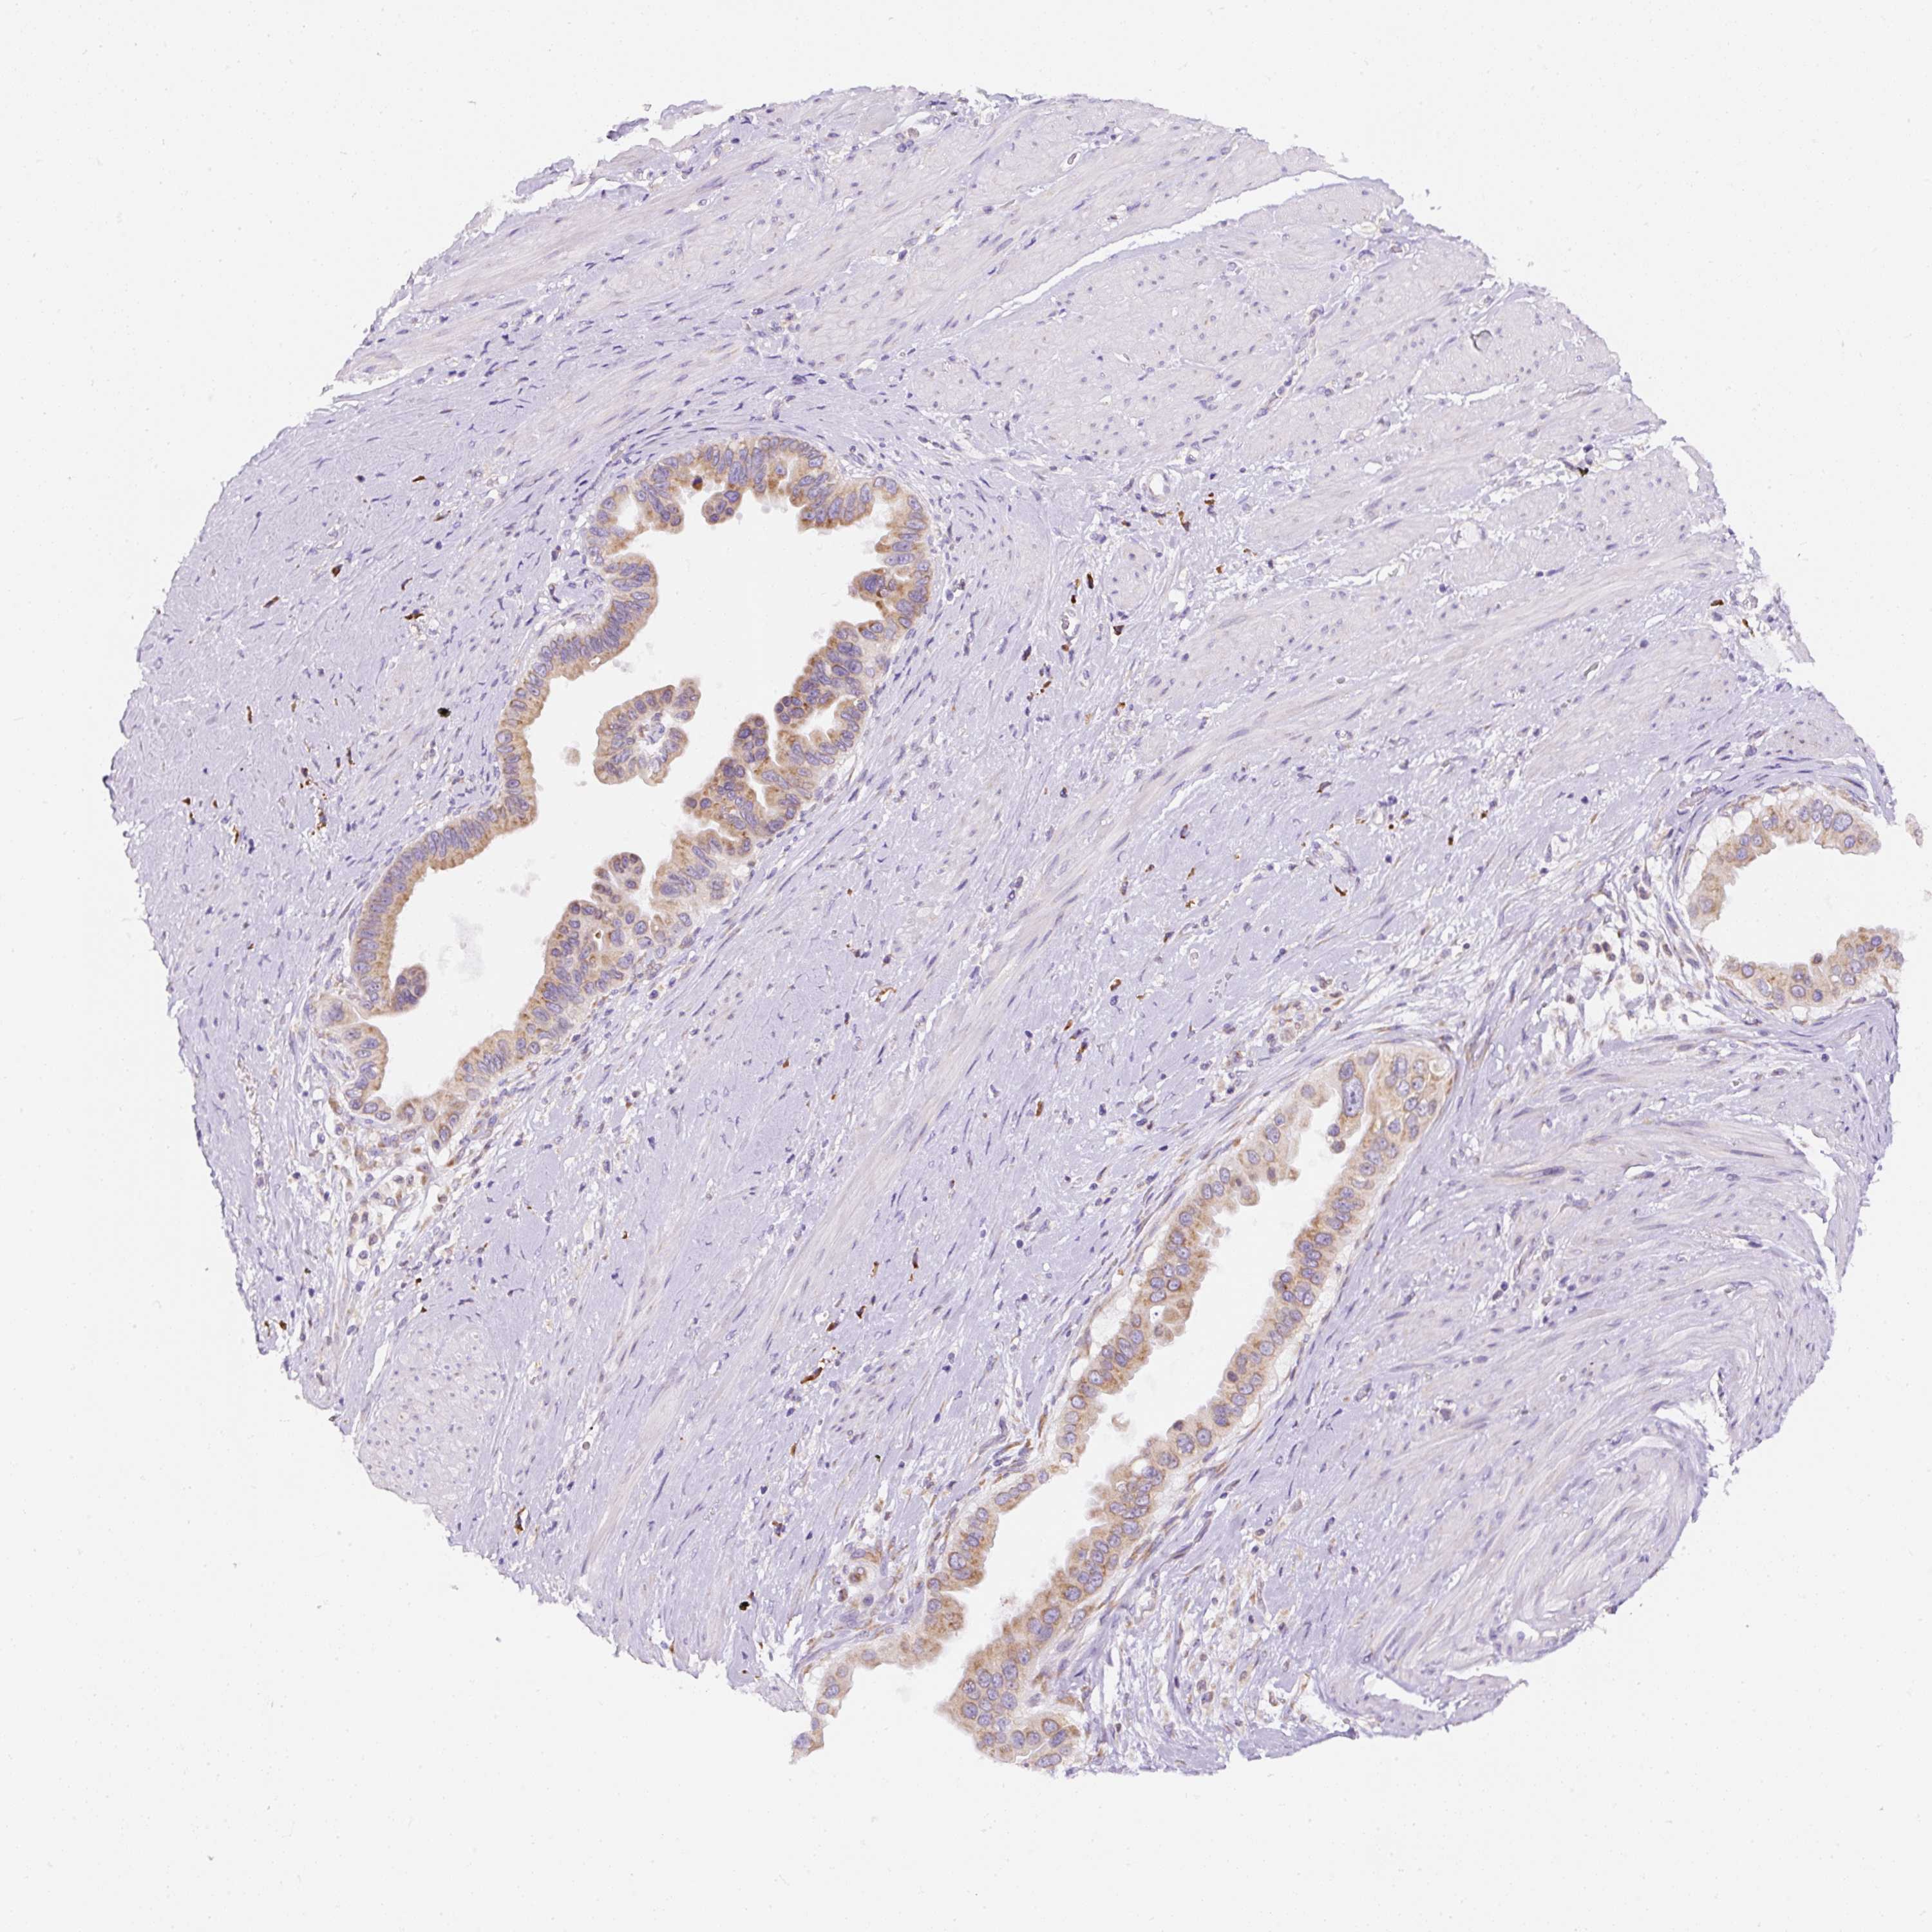

PANCREATIC CANCER - Protein expressioni

A mouse-over function shows sample information and annotation data. Click on an image to view it in a full screen mode. Samples can be filtered based on level of antibody staining by selecting one or several of the following categories: high, medium, low and not detected. The assay and annotation is described here.

Note that samples used for immunohistochemistry by the Human Protein Atlas do not correspond to samples in the TCGA dataset.

Antibody stainingi

Antibody staining in the annotated cell types in the current human tissue is reported as not detected, low, medium, or high, based on conventional immunohistochemistry profiling in selected tissues. This score is based on the combination of the staining intensity and fraction of stained cells.

Each image is clickable and will lead to virtual microscopy that enables deeper exploration of all samples and also displays staining intensity scores, fraction scores and subcellular localization as well as patient and tissue information for each sample.

Antibody HPA046841

Antibody HPA052867

Antibody CAB009746

Staining

High

Medium

Low

Not detected

Intensity

Strong

Moderate

Weak

Negative

Quantity

>75%

75%-25%

<25%

None

Location

Nuclear

Cytoplasmic/membranous

Cytoplasmic/membranous,nuclear

Adenocarcinoma, NOS

Adenocarcinoma, metastatic, NOS